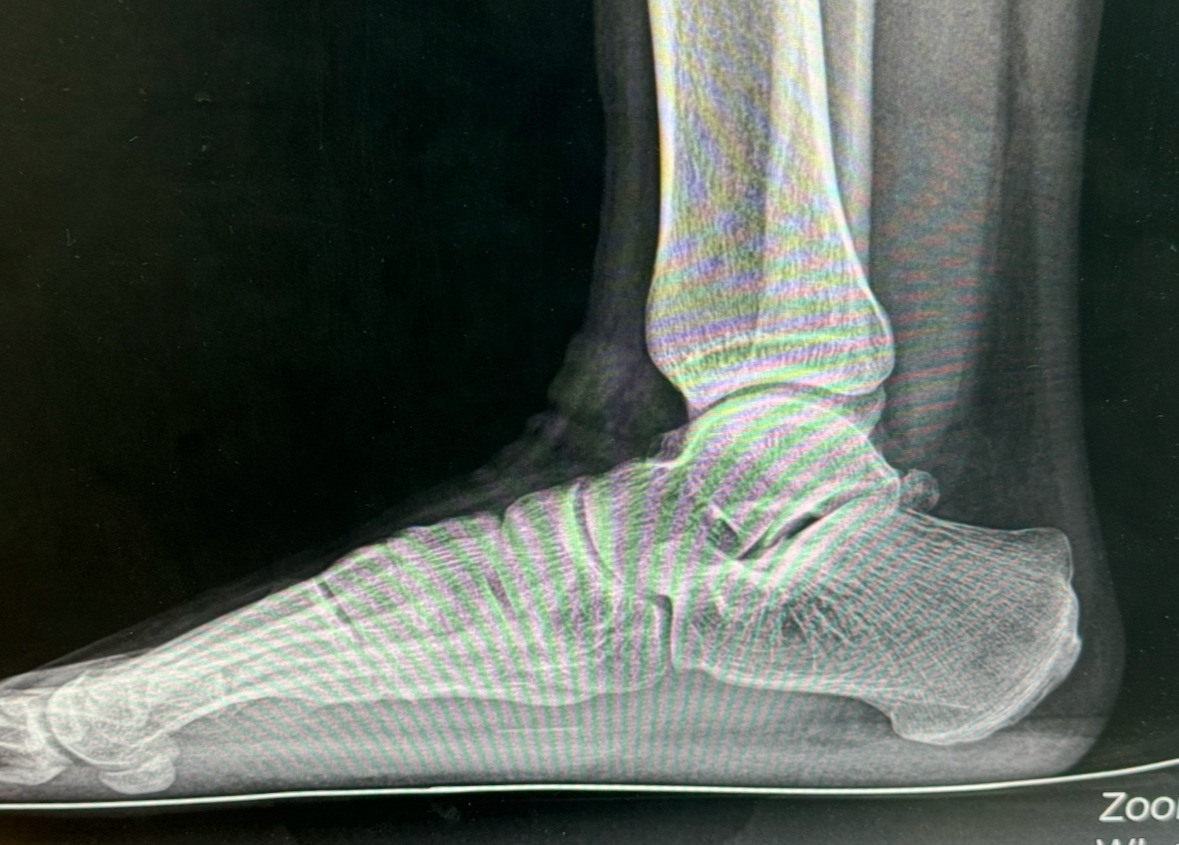

낙엽이 떨어지고 눈이 많이 내렸다. 첫 사고 날로부터 1년 2개월이나 흘렀다. 마지막 수술을 끝내고 줄기세포를 넣었기 때문에 의사 선생님께서 1달 동안 발을 딛지 말라고 하셨다. 발을 딛기 전 확실히 이전보다 훨씬 나아진 느낌이 들었다. 하지만 의사 선생님은 발을 딛고 걷기 전 까진 모른다고 하셨다.

마지막 수술 후 1달이 지나고 발을 딛고 걷는 연습을 시작했다. 양옆 복숭아뼈의 통증은 좀 있었지만 오래 걸으니 조금씩 사라졌다. 병원에서 배운 헬스기구를 이용한 재활도 열심히 했다. 점점 똑바로 걸어지기 시작했다. 빨리 보통의 삶으로 돌아가고 싶어서 재활하는 시간을 늘리고 열심히 하였다. 그리고 한 달 후 의사 선생님과 약속한 검진날 병원을 방문했다. 나는 의사 선생님께 이전보다 확실히 나아졌고 뒷꿈치과 복숭아뼈에 좀 통증이 있다고 하였다. 의사 선생님은 통증은 많이 걸으면 사라질거라고 하셨다.

검진 후 재활을 더욱 열심히 하였다. 올해가 한 달 밖에 안 남았기 때문에 올해가 가기 전 절뚝거리는 것을 없애고 싶었다. 하지만, 어느 순간부터 아킬레스건 양옆이 부어오르기 시작하면서 뒤꿈치까지 통증이 심해졌다. 수술할 때 아킬레스건을 늘리는 수술도 같이 했다는 의사 선생님의 말이 떠올랐다. 인터넷에 검색해 보니 아킬레스건 파열 수술을 한 환자들이 수술 후 아킬래스건 염이 발병하여 나와 같은 통증을 겪는다는 정보를 얻었다. 그들은 오래 걸으면 나아진다는 의견이 있는 반면, 더 심각해 지기 전에 빨리 병원에 가보라는 의견도 있었다. 걱정이 되기 시작했다.

그나마 수술 한 발목 앞쪽 부위는 아무런 통증이 없어 다행이라는 생각도 했다. 아킬레스건 양옆의 통증은 걸을 때마다 지속적으로 생기는데 걷기 힘들 정도로 심해졌다. 그리고 이 통증은 피로감을 증폭시킨다. 찢어지는 고통은계속 되어서 병원에 전화해서 예약을 하려고 하니 일주일 후에나 가능하다고 답변을 받았다. 아킬래스건 염은 많이 걸으면 나아진다고도 하니 일단은 계속 걸어보려 한다. 심각한 증상이 아니길 바라는 수밖에 없다.